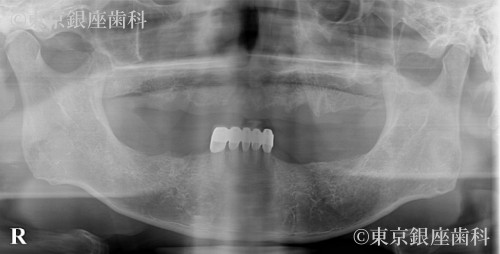

高額見積もりからセカンドオピニオンで最適治療を選択し噛める機能を獲得した80歳代男性の症例

Before

疾患 歯牙部分欠損

他院で1500万円超の提案を受け不安になり当院受診。精密診断の結果、片顎4本で十分と判断し上下ワンデイを実施。禁煙にも成功し現在も安定。

上下ワンデイインプラント